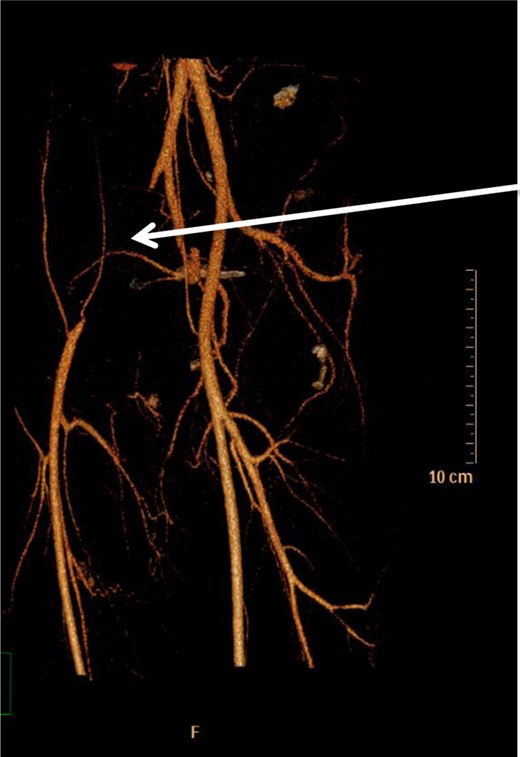

He presented to his general practitioner 2 weeks later with claudication. His symptoms included pain and paraesthesia in his right buttocks on mobilization >100 m. He was found to have absent peripheral pulses in his right leg, although it appeared well perfused with a normal capillary refill. An arterial Doppler ultrasound showed a right external iliac artery thrombus occluding the proximal two-thirds of the vessel. A computed tomography scan of the abdomen and pelvis with intravenous contrast identified complete occlusion of the right external iliac artery ∼1 cm beyond its origin. However, the common femoral artery and profunda femoris remained patent via collaterals (Fig. 1).

Occlusion of right external iliac artery 1 cm below its origin (white arrow). The right common femoral artery is supplied by inferior epigastric and lateral thigh collaterals. Left-sided vessels are normal.